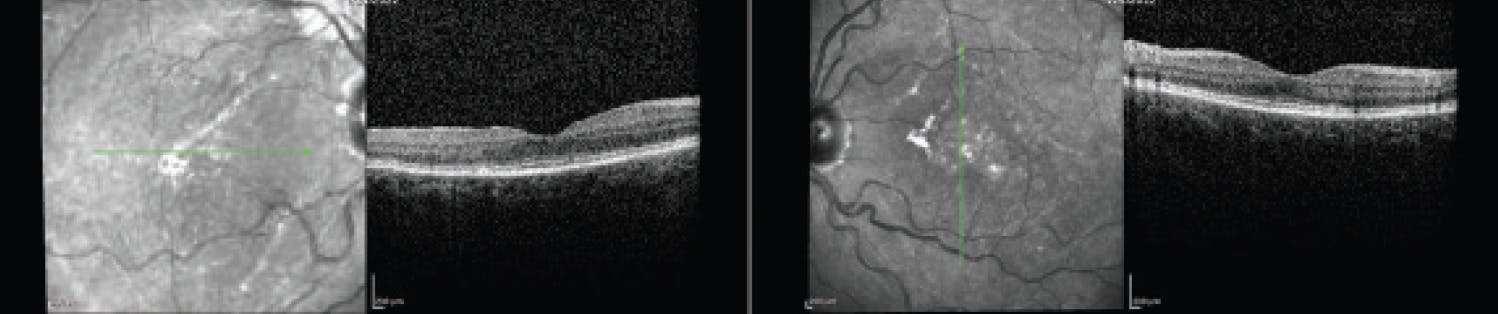

One example from my practice merits mention: An obese 20-year-old Hispanic woman presented some years ago in big-time visual distress with headaches, tinnitus, VA of counting fingers OU, diffuse choroidal melanocytosis, and walloping serous retinal detachments. This constellation of complaints and findings seemed a near lock for VKH, as did ancillary imaging that demonstrated retinal pigment epithelium undulations on OCT suggestive of acute disease (Figure 1).1 Fluorescein angiography provided further corroboration and was notable for clusters of pinpoint angiographic leaks (Figure 2).

<p>Figure 1. The patient’s OCT demonstrates retinal pigment epithelium undulations, suggesting acute VKH.</p>

Figure 1. The patient’s OCT demonstrates retinal pigment epithelium undulations, suggesting acute VKH.

<p>Figure 2. Fluorescein angiography demonstrates clusters of pinpoint angiographic leaks in each eye.</p>

Figure 2. Fluorescein angiography demonstrates clusters of pinpoint angiographic leaks in each eye.